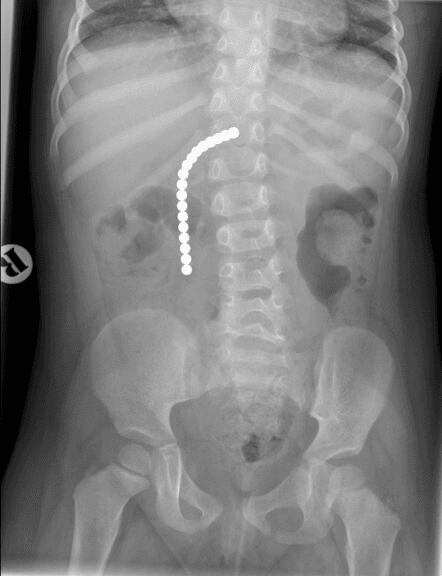

En el Royal Hospital for Children de Glasgow, la radiografías mostraron que algo estaba bloqueando el funcionamiento de los intestinos de Jack, para luego descubrirse que se trataba de una colección de imanes, por lo que el menor de 9 años admitió que se había tragado estos.

La operación duró 4 horas y durante la intervención Jack Mason perdió el intestino delgado, una porción del grueso, así como el apéndice. Ocho días después de pasar por el quirófano, el niño fue dado de alta.